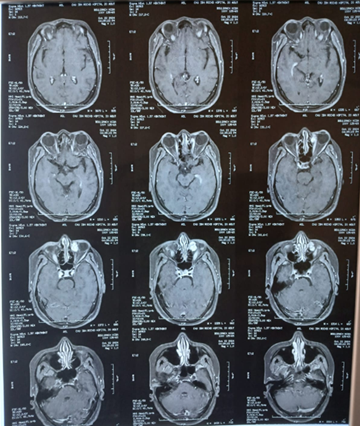

Orbital cavernomas are

the most frequent benign orbital tumor. They are slow-growing lesions of the

intracanal space. A 58-year-old female presented for 7 months of impaired

visual acuity of the left eye associated with severe pain. The physical

examination showed left axial proptosis. Orbital magnetic imaging revealed a 21

mm diameter extraconal space of the left orbital space. The patient underwent

an endoscopic, minimally invasive procedure (FESS) with resection of the tumor

trans nasally.